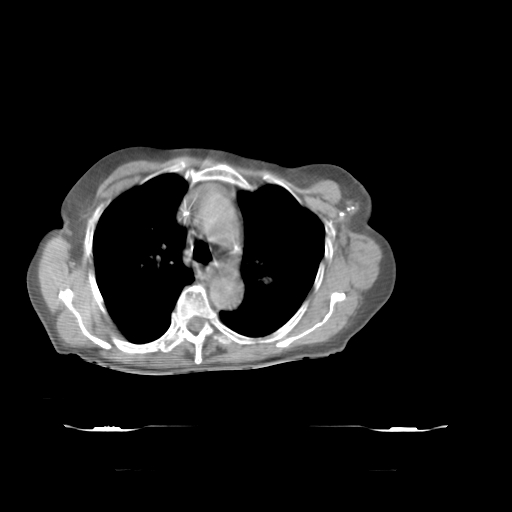

Planning CT Images